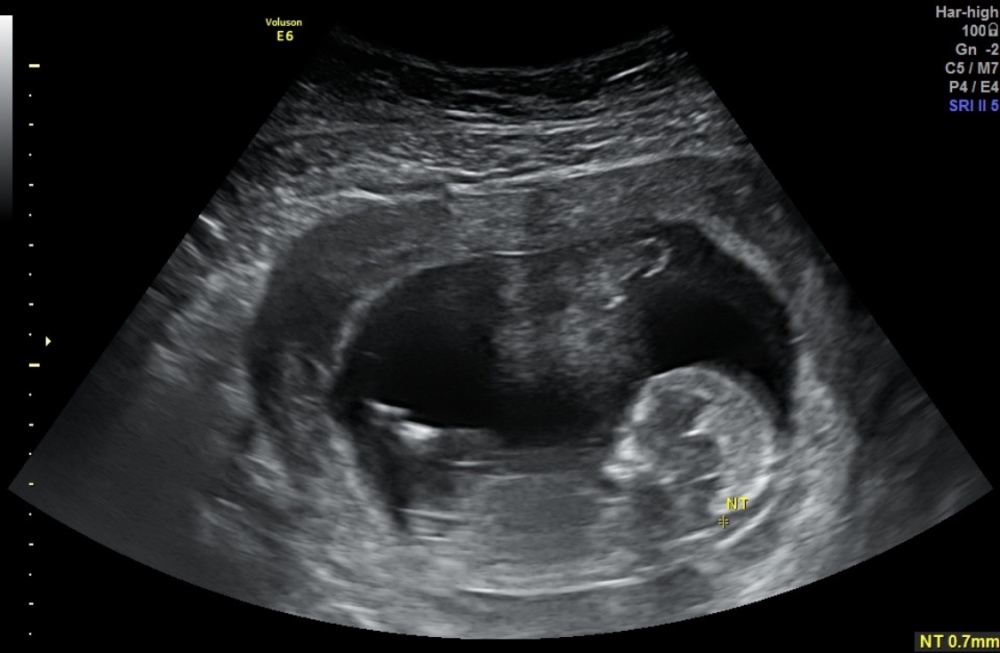

Heute hatte ich den Termin zur Nackenfaltenmessung. Habe ein US-Bild mitbekommen und hoffe ihr könnt da was erahnen bzw eine Tendenz abgeben?

7